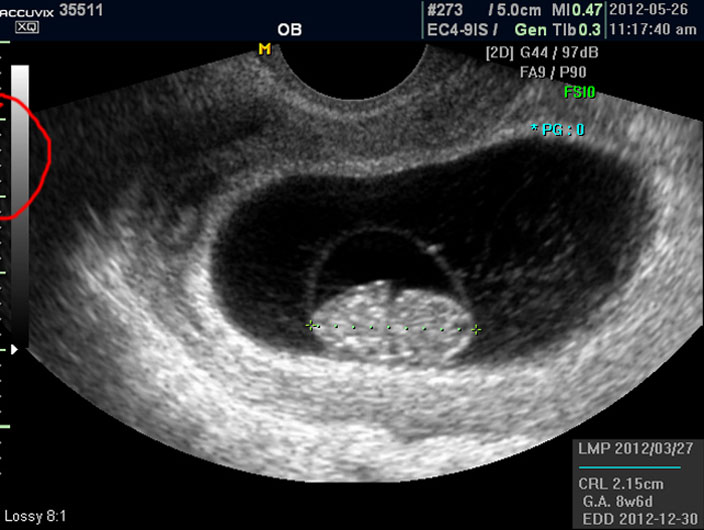

그리고 초음파 검사에서는 산전 초음파 이외의 다른 경우도 그렇지만 물에 가까운 성분일수록 검게 나오고 뼈처럼 단단해서 초음파 선이 투과하지 못하는 부분은 하얗게 나타납니다.

이는 투과 선은 다르지만 X 레이 검사 사진에서도 마찬가지입니다.

따라서 하얗게 보이는 태아 주변의 검은 부분은 양수입니다.

이 양수의 양은 아기의 건강과 밀접한 관련이 있기는 하지만 그 절대적 양을 측정하기는 어려워서 몇군데 부위를 체크하여 많은지 적은지를 판단합니다.

물론 임신 중기 이후 양수 과소증이나 양수 과다증이 의심될 경우이며 일반적으로는 1차원적으로 봤을 때 양수의 가장 긴 길이가 태아 크기의 2배에서 4배 정도의 길이를 차지하지만 이 길이나 양은 임신 주기에 따라 다르기 때문에 정확한 것은 아니며 또한 임신 말기로 갈수록 상대적으로 양수의 양이 줄어듭니다.

양수는 태아의 소변으로 만들어지고 태아가 폐나 위로 흡수해서 소멸하기 때문에 항상 변동이 되는 부분입니다.

양수 바깥의 조금 회색으로 보이는 얼룩덜룩한 부분이 아기를 품고 있는 자궁이며 근종이나 기타 이상은 없는지 체크하지만 여기서는 산과 부분만 설명하기로 했기 때문에 따로 설명드리지 않습니다.